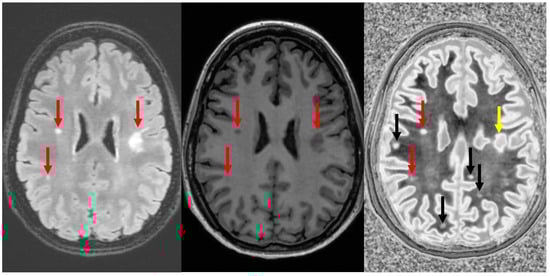

Figure 11.

Divided Subtracted Inversion Recovery (dSIR) in a patient with multiple sclerosis (MS). T2-FLAIR (left), inversion recovery (IR) T1-weighted (middle), and wide-domain dSIR with TIshort = 450 ms and TIlong = 850 ms (right) images through the pons in a patient with MS. A large plaque is obviously present in the left hemipons on the dSIR image (red arrow in the image on the far right). The contrast in this image is due to changes in white matter T1. The change in T1 is insufficient to cause noticeable contrast on the IR T1 image (middle). The change in T2 is insufficient to cause noticeable contrast on the T2-FLAIR image (left).

Figure 12.

Divided Subtracted Inversion Recovery (dSIR) in a patient with multiple sclerosis (MS). T2-FLAIR (left), inversion recovery (IR) T1-weighted (middle), and wide-domain dSIR with TIshort = 450 ms and TIlong = 850 ms (right) images through the upper corona radiata in a patient with MS. Three plaques are seen on the T2-FLAIR and IR T1 images (red arrows). More plaques are seen on the dSIR image (black arrows). The plaque in the left frontal white matter is seen on the dSIR image (yellow arrow) but, due to the high signal etching along its margins, could easily be mistaken for cortex.